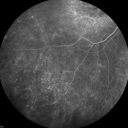

Fluorescein Angiogram - Enhanced S Cone Syndrome - Goldmann Favre - 738 views55-year-old woman while in college her vision was poor even with glasses and she sought evaluation for that. She was told after she had an electroretinogram at USF 15 years ago, that she had something with her blue cones. She does have poor night vision, but her reading vision is pretty good.

VISUAL ACUITY: OD 20/40, OS 20/40     (0 votes)

FLUORESCEIN ANGIOGRAPHY: Fluorescein angiography shows speckled hyperfluorescence in the macula of the right eye, a little bit of a bull’s eye type pattern. There is some loss of the macular pigment and then throughout the periphery there is increased hyperfluorescence. The retinal vessels are attenuated, but nothing leaks. The fluorescein angiogram of the left eye is similar and it is symmetric to the other eye and shows hyperfluorescence ringing the macula.